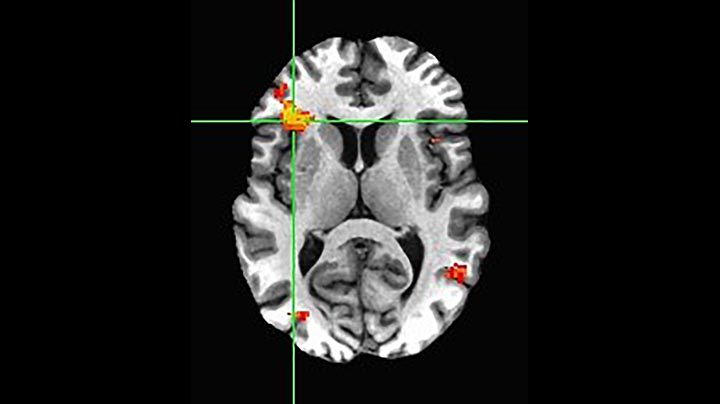

The principle of MultiBand SENSE:

simultaneous slice excitation and sensitivity reconstruction

MultiBand SENSE starts with the simultaneous excitation of two or more slices, while the acquisition readout is unchanged. So, the base resulting image is actually an accumulated image of all excited slices. However, similar to normal SENSE algorithms, the signal can be unfolded to reveal the separate images. This unfolding can be complicated when coil sensitivity profiles are similar for the separate slices. Therefore, the MultiBand SENSE technique employs a phase shift during excitation to simplify the unfolding process, and virtually eliminate artifacts generated by residual aliasing and noise enhancement [5]. The result is that MultiBand SENSE can acquire multiple slices in a time identical to that of a single slice acquisition, which thus provides a significant acceleration. The acceleration is chosen via the MultiBand SENSE factor that indicates the number of simultaneously acquired slices, which is always an integer number.

MultiBand SENSE

Simultaneous acquisition of multiple slices to accelerate fMRI and dMRI in the brain. A phase shift between slices is used to facilitate SENSE unfolding for obtaining the individual images.